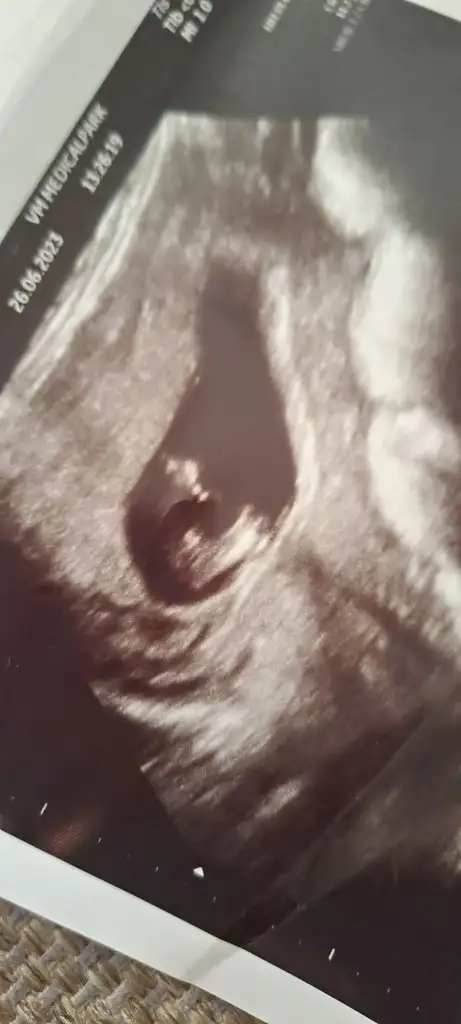

Hanımlar cinsiyet tahmini alabilir miyim 12+1 günlüğüz birde cinsiyeti erkek olanların ultrasyon fotolarını görebilir miyim acaba ocak anneleri benimde 7 ocak dogumum insallah attığım fotolar bacak arası bu arada teşekkür ederim şimdiden

• 20230626_152119.webp

18,3 KB · Görüntüleme: 145

Renkli ultrasyonda var yandan canım atıyorum şimdi. Dr şey dedi dik değil çıkıntı dedi ondan erkek diyemem dedi ama bilmiyorum

Evet nubu aşağıya bakıyormış gibi ama bak bi şişkinlik çıkıntı burda da var